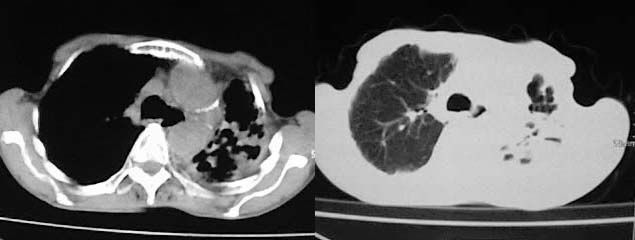

以下是引用有风的日子在2008-5-2 12:13:00的发言:[br][emb10][br][br]肺ca?有病理支持吗?[br][br]我看更象是肺tb并支扩、间质性肺炎。最好拿个病理结果来,不然这点影像资料诊断肺ca是难以服人的![br][br]至于主动脉瘤的诊断问题,国外认为≥4.0cm就可诊断了,国内对此诊断标准更为严格。患者升主动脉明显增粗,即>4cm。你诊断个升主动脉扩张并不为过!

以下是引用zjzjr在2008-5-2 14:39:00的发言:[br]支持双侧继发型肺结核,左侧胸膜肥厚,慢性支气管炎伴间质纤维化.